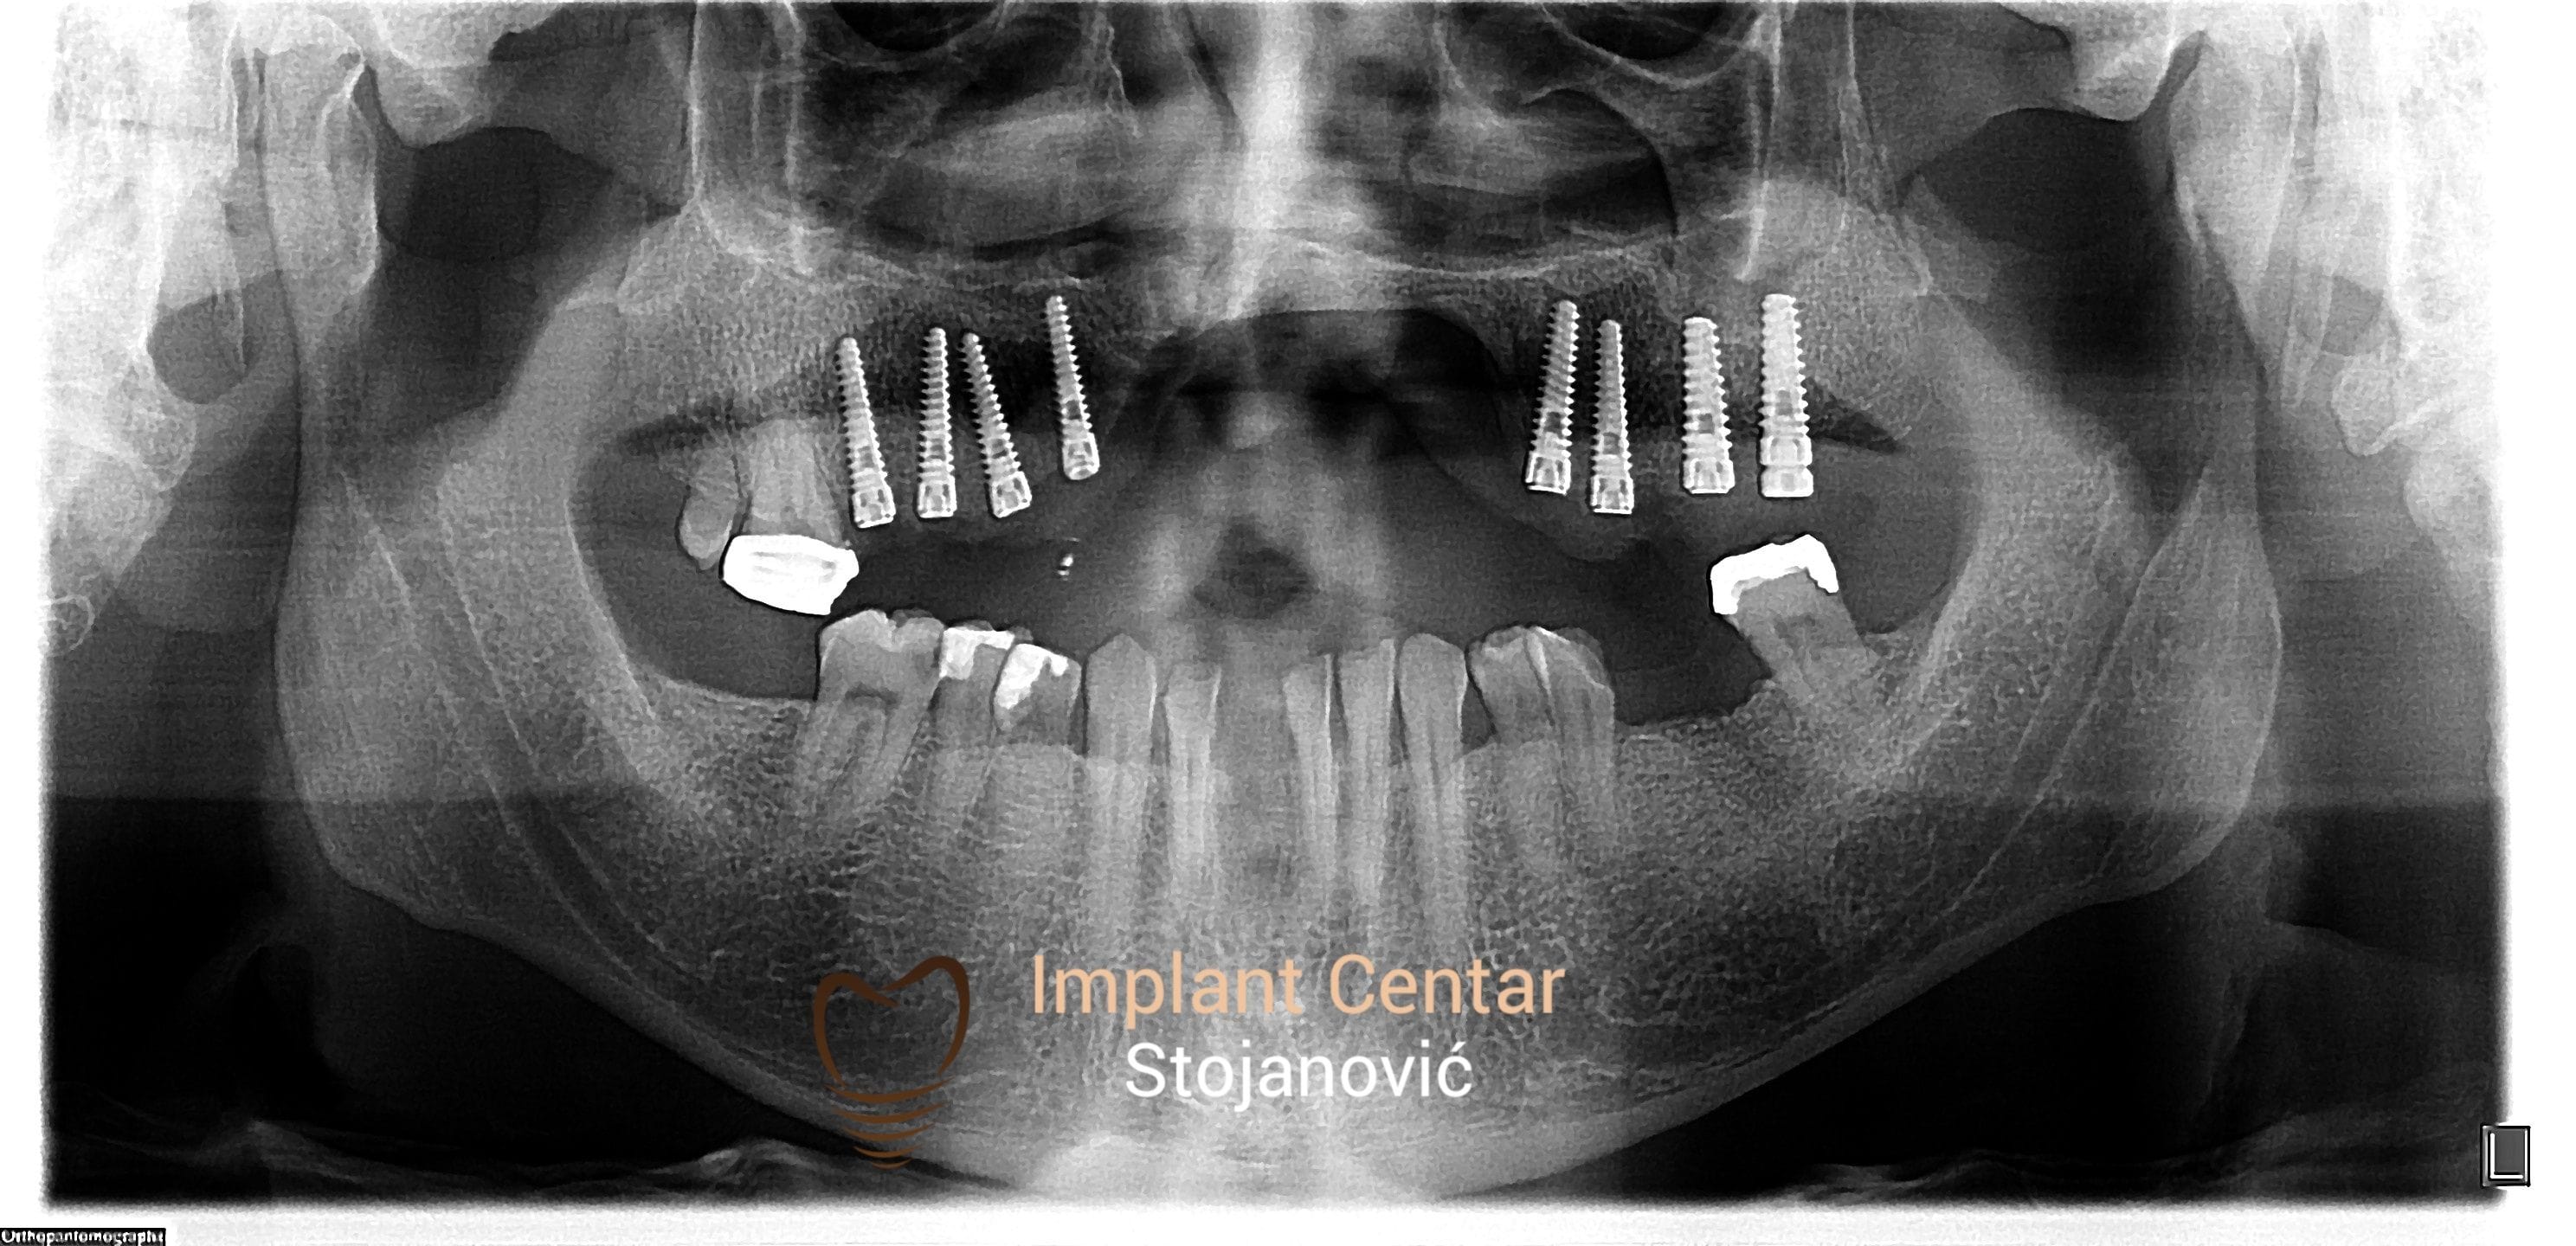

Implantno-protetska sanacija defekta gornje vilice uzrokovanog ratnom traumom

PRISTUPILI SMO RESAVANJU DEFEKTA GORNJE VILICE SA CILJEM MAKSIMALNOG KOMFORA I SIGURNOSTI ZA PACIJENTA UGRADNJOM IMPLANTATA I IZRADOM FIKSNOG METALOKERAMICKOG MOSTA

Pre Posle